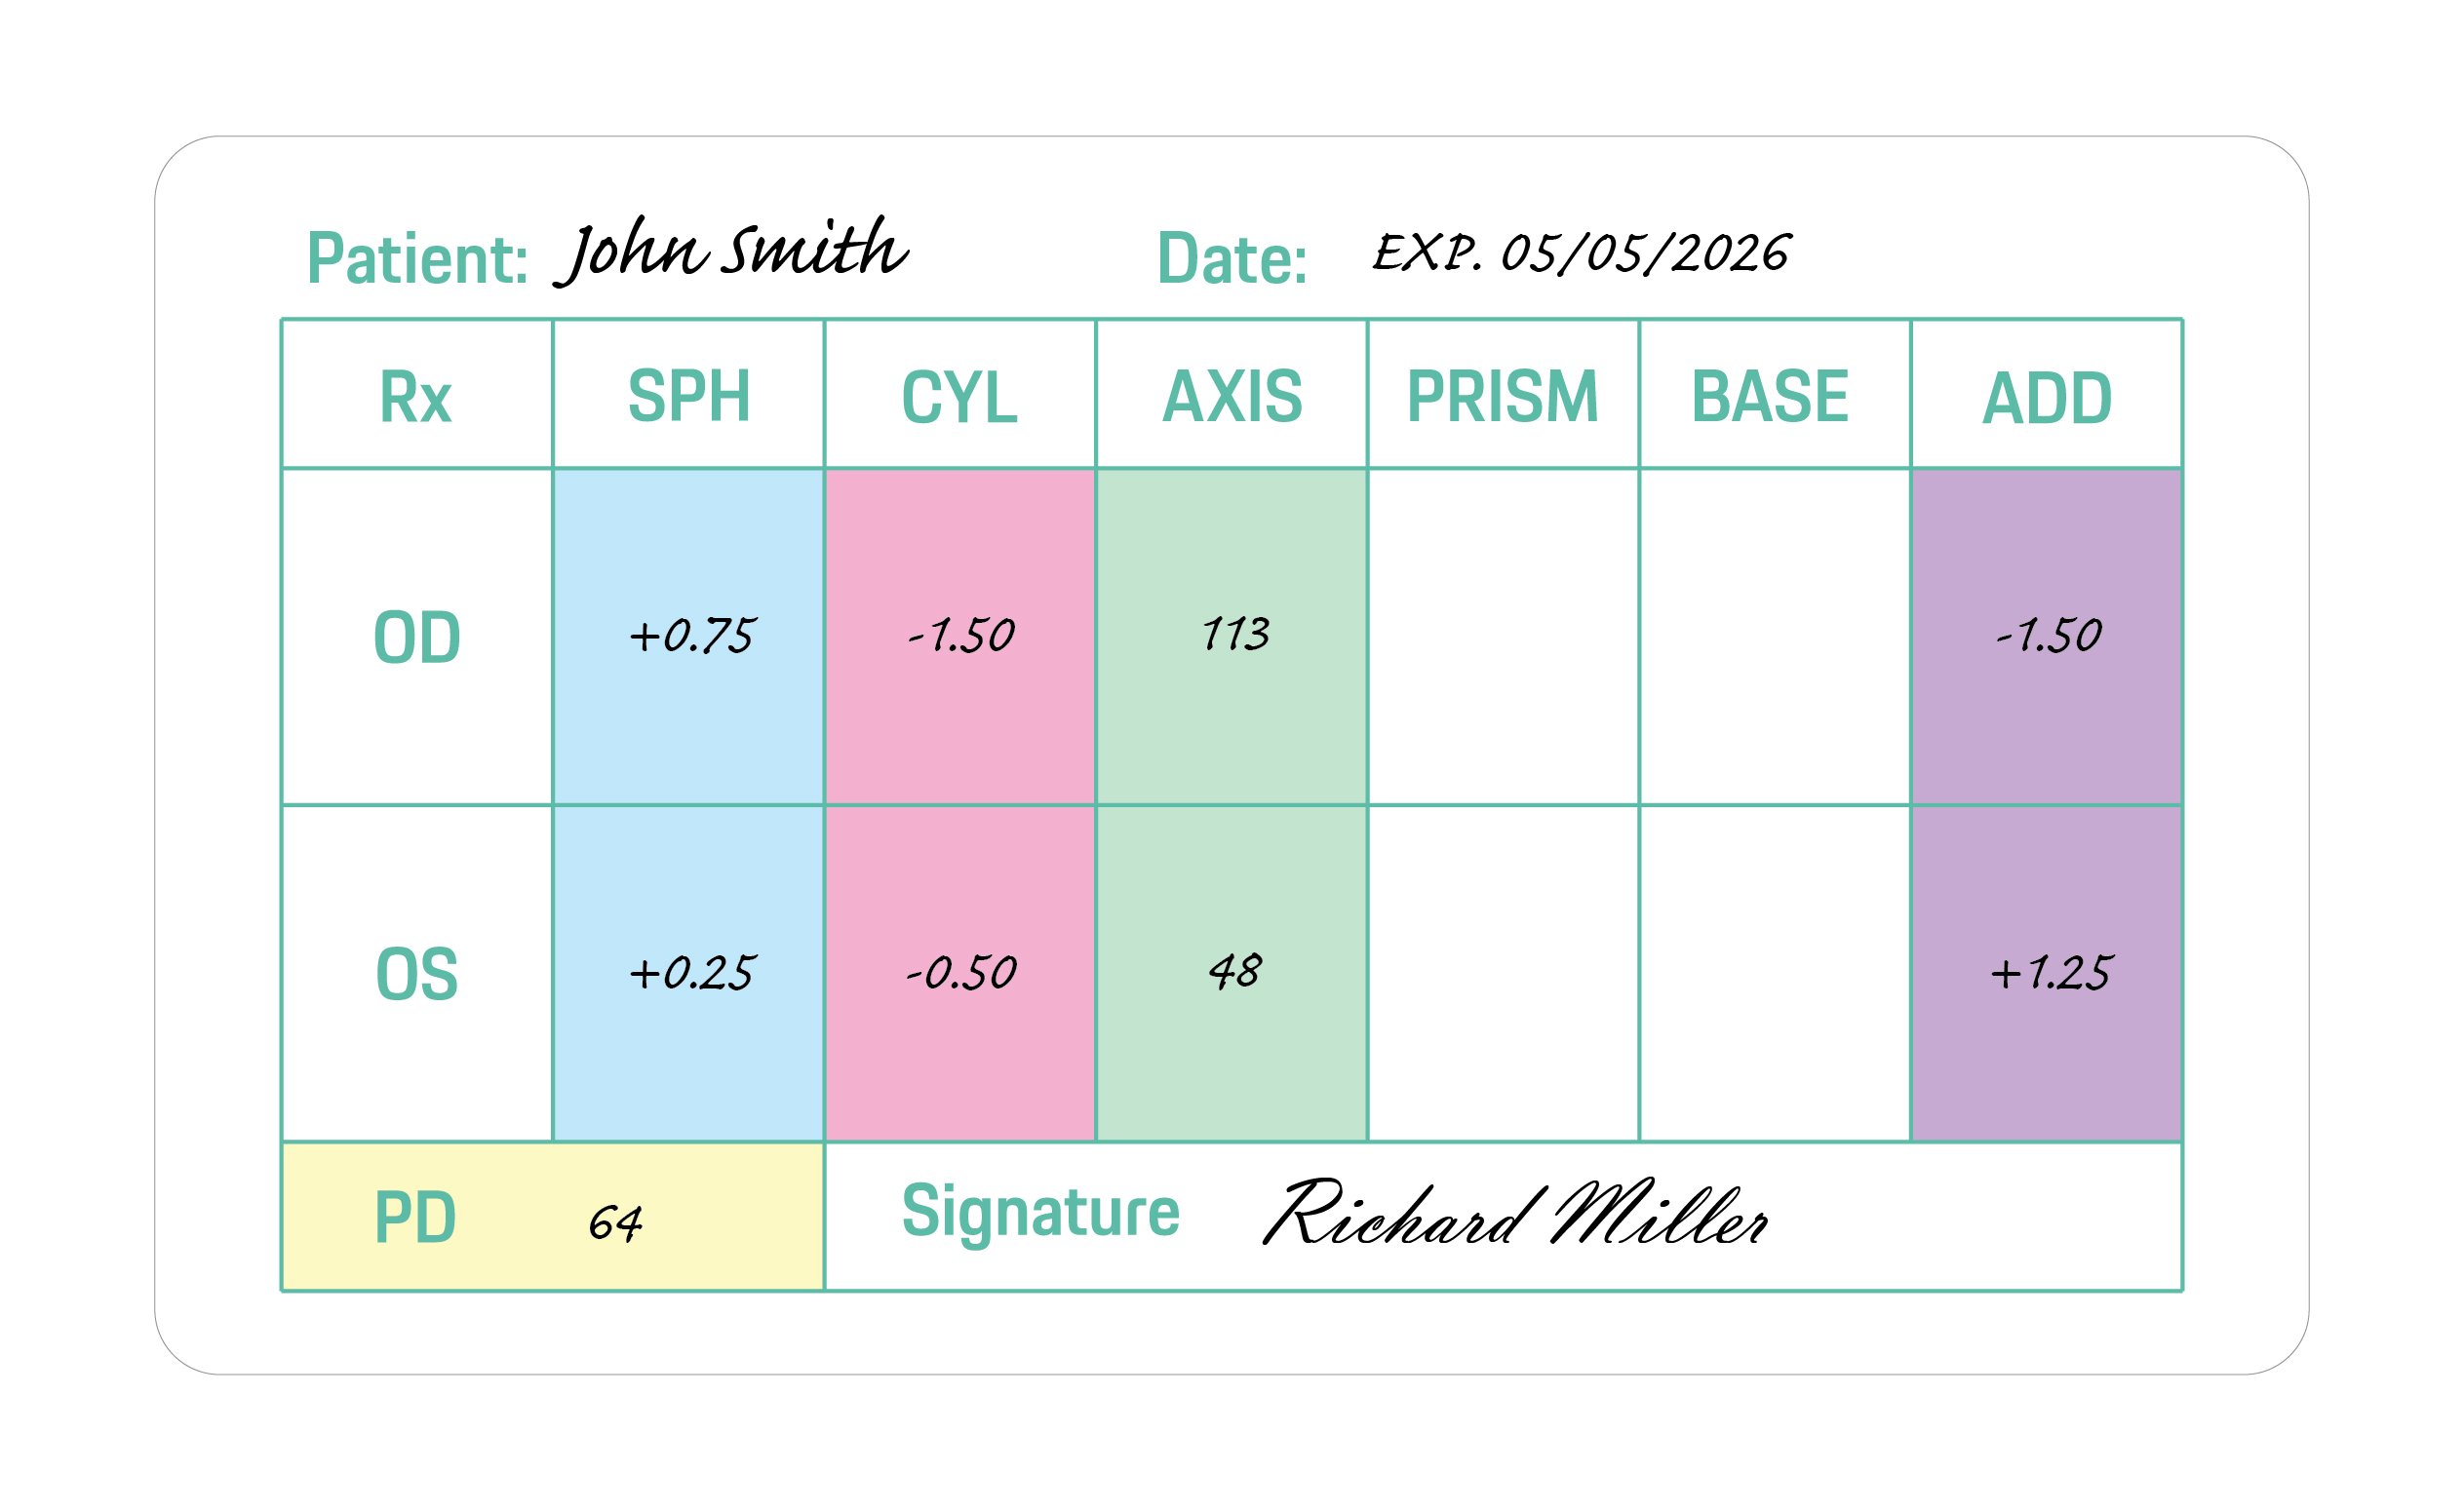

OD is an abbreviation for the Latin term oculus dexter which means right eye. Notice that the right eye information is asked for first even though we typically read from left to right.

OS is an abbreviation of the Latin oculus sinister which means left eye. That will be referenced on the far right column of the prescription.

SPH is short for sphere. The sphere of your prescription indicates the power on the lenses that is needed to see clearly. A plus (+) symbol indicates the eyeglass wearer is farsighted. A minus (-) symbol indicates that the eyeglass wearer is nearsighted.

CYL is short for cylinder. The cylinder indicates the lens power necessary to correct astigmatism. If the column has no value (is blank), it indicates that the eyeglass wearer does not have astigmatism. If this is the case on your prescription, you can leave it blank when entering it in.

AXIS is a prescription will include an axis value for those with astigmatism. This number represents the angle of the lens that shouldn't feature a cylinder power to help correct your astigmatism.

ADD is short for "additional correction." This is where details about bifocals, multifocal lenses or progressive lenses would appear.